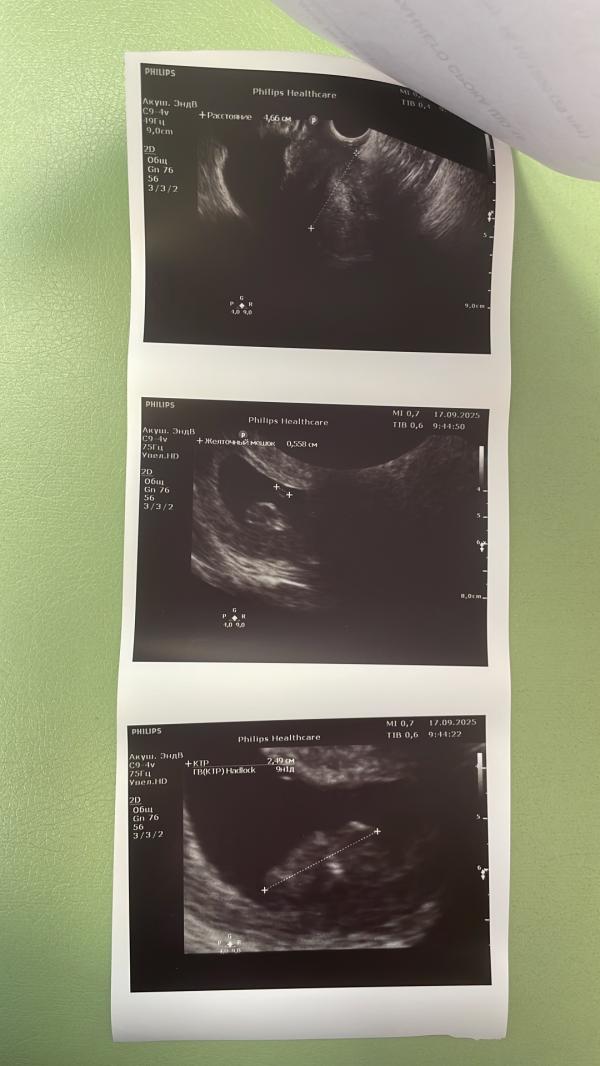

14.08 делаю Узи и да беременность, но без жизнедеятельности, но конечно же всё развилось и сердечко услышали и увидели❤️

А теперь нам уже 14 недель, мы растём.